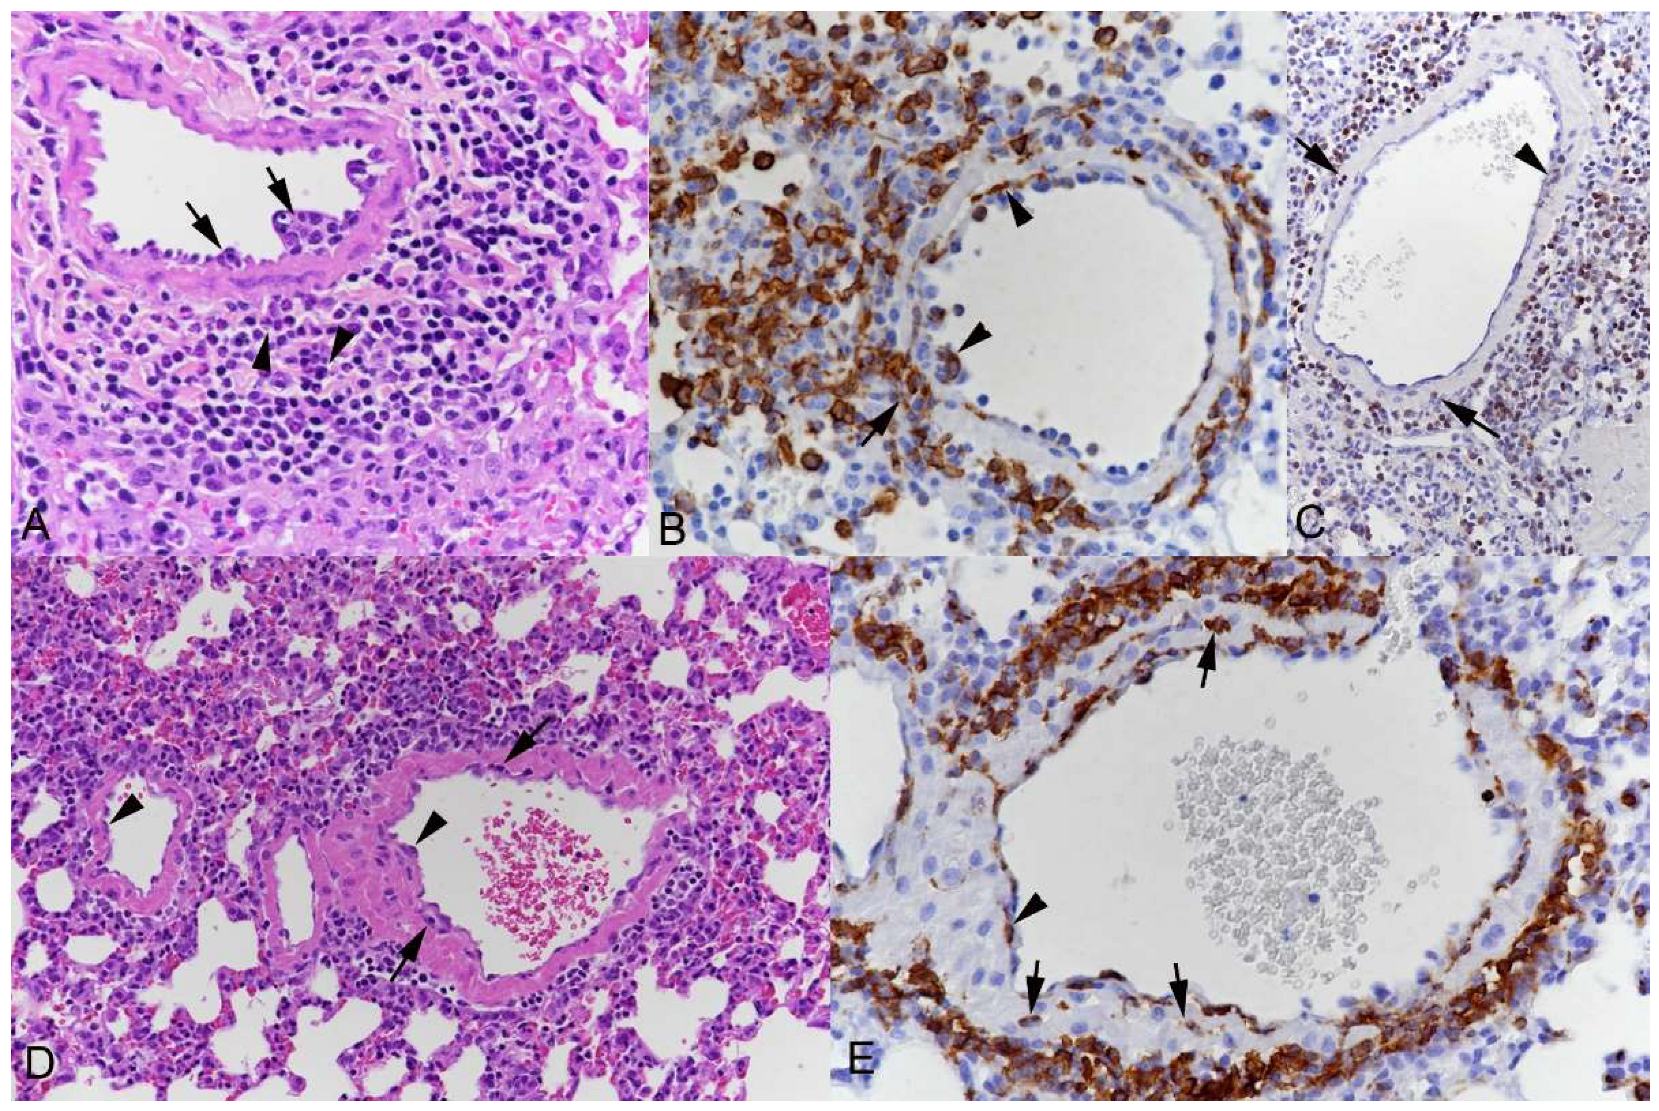

3.1. Pulmonary Vasculitis Is a Consistent Feature of SARS-CoV-2 Infection in Mouse Models

3.2. Respiratory Virus Infections, with Variable Degree of Alveolar Damage, and with or without Damage to Respiratory Epithelium, Elicit a Stereotypic Vascular Response